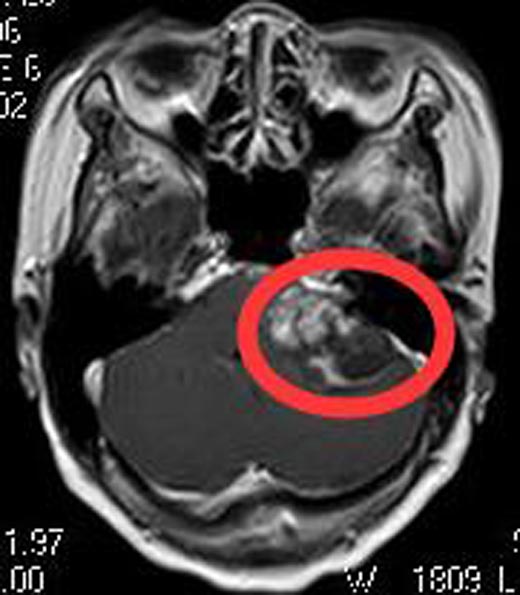

入住广东三九脑科医院综合神经外科,头颅MR检查提示:左侧桥小脑角区占位性病变,大小约为4.4cm×3.3cm×2.4cm,考虑听神经鞘瘤。头颅CTA检查提示:左侧桥小脑角区占位病变,其内血管丰富,考虑听神经瘤可能。

完善术前检查后,由鲁明主任主刀,在全麻下行左侧桥小脑角区占位切除术,术中显微镜下见肉红色肿瘤组织,包膜完整,被小脑前下动脉包绕,血供丰富,显微镜下见肿瘤上至三叉神经,下达末组颅神经,与面听神经及脑干明显粘连;予分块全切除肿瘤,相邻神经、血管保护满意,面听神经解剖保留,手术过程顺利。术后黄阿姨没有面瘫、嘴角歪斜、饮水呛咳等后组颅神经损害症状,听力明显好转,康复出院。术后病理结果提示:神经鞘瘤。